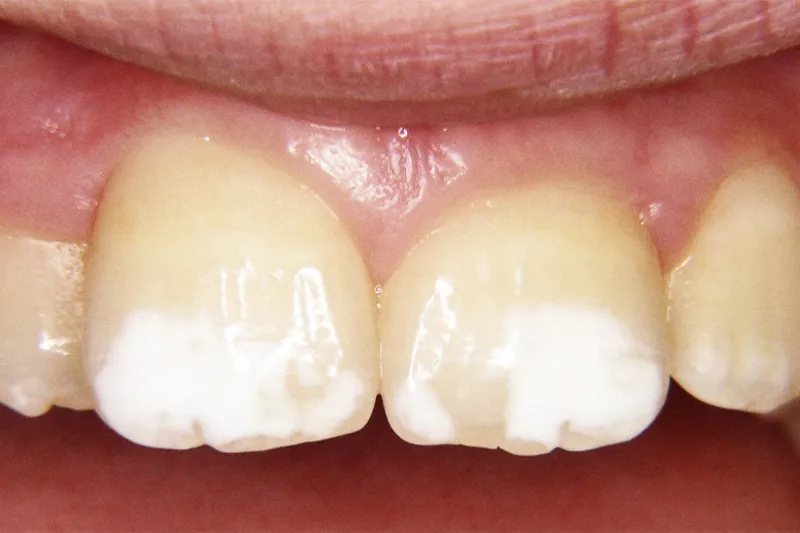

Resultater – Den globale prævalens af MIH er beregnet til 14,2 %. Der er påvist tilsvarende forstyrrelser på anden primære molar og på kusptoppene på de permanente molarer. Emaljens mikrostruktur, mekaniske egenskaber og kemiske sammensætning er ens hos første permanente molarer og primære molarer, der er ekstraheret pga. kraftige MIH-læsioner med sammenbrud. Ætiologien er ikke afklaret. Flere systemiske og genetiske og/eller epigenetiske faktorer, som agerer synergistisk eller additivt, kan knyttes til MIH, og det tyder på en multifaktoriel ætiologisk model. Seksårstænder med mineralisationsforstyrrelser er problematiske for de børn, der rammes. Tænderne isner allerede ved frembruddet, det er pinefuldt og vanskeligt at børste dem og at indtage mad og drikke, hvilket påvirker barnets livskvalitet og velbefindende.

Konklusion – MIH har store konsekvenser i form af smerte, caries, hyppige behandlinger samt æstetiske problemer. Der mangler langtidsundersøgelser af forskellige behandlinger, og der er kun få og mangelfulde studier om de ramte børns erfaringer.

Results – The global prevalence of MIH has been estimated to 14.2 %. Similar defects in the tip of permanent canines and second primary molars have been reported. The microstructure, mechanical properties chemical composition in enamel from first permanent molars and second primary molars extracted as a consequence of severe enamel hypomineralization and disintegration are similar. The etiology is still obscure. Some systemic and genetic and/ or epigenetic factors acting synergistically or additively are associated to MIH indicate a multifactorial model. First permanent molars with MIH are problematic for the affected children. From eruption, the teeth cause shooting pain. Brushing teeth is painful and caries risk is raised. Also eating and drinking is uncomfortable and influence the wellbeing and quality of life.

Conclusions – MIH leads to pain, caries, repeated treatments and aesthetic problems. Long term follow ups of various treatment are missing. Studies of the experience of the affected children are few and insufficient.